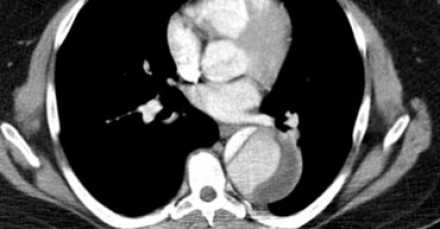

- Гемиперикард, гемомедиастенум и гемиторакс являются грозными осложнениями диссекции аорты.

- Ниже представлен пациент с полным тромбированием ложного просвета. Спустя 5 дней после первого обращения пациент жалуется на резкую боль в груди, а снимках визуализируется кровоток в ложном просвете.

- Увы, но пациентка не могла продолжить лечение хирургически по разным причинам, поэтому лечилась медикаментозно.

- Порой сложно дифференцировать тромбированный просвет при диссекции и аневризму с тромбом.

- Если интима кальцинированна, то это очень помогает.Слева — тромбированный просвет при диссекции. Справа — аневризма с тромбом на внутренней стороне кальцинированной интимы.